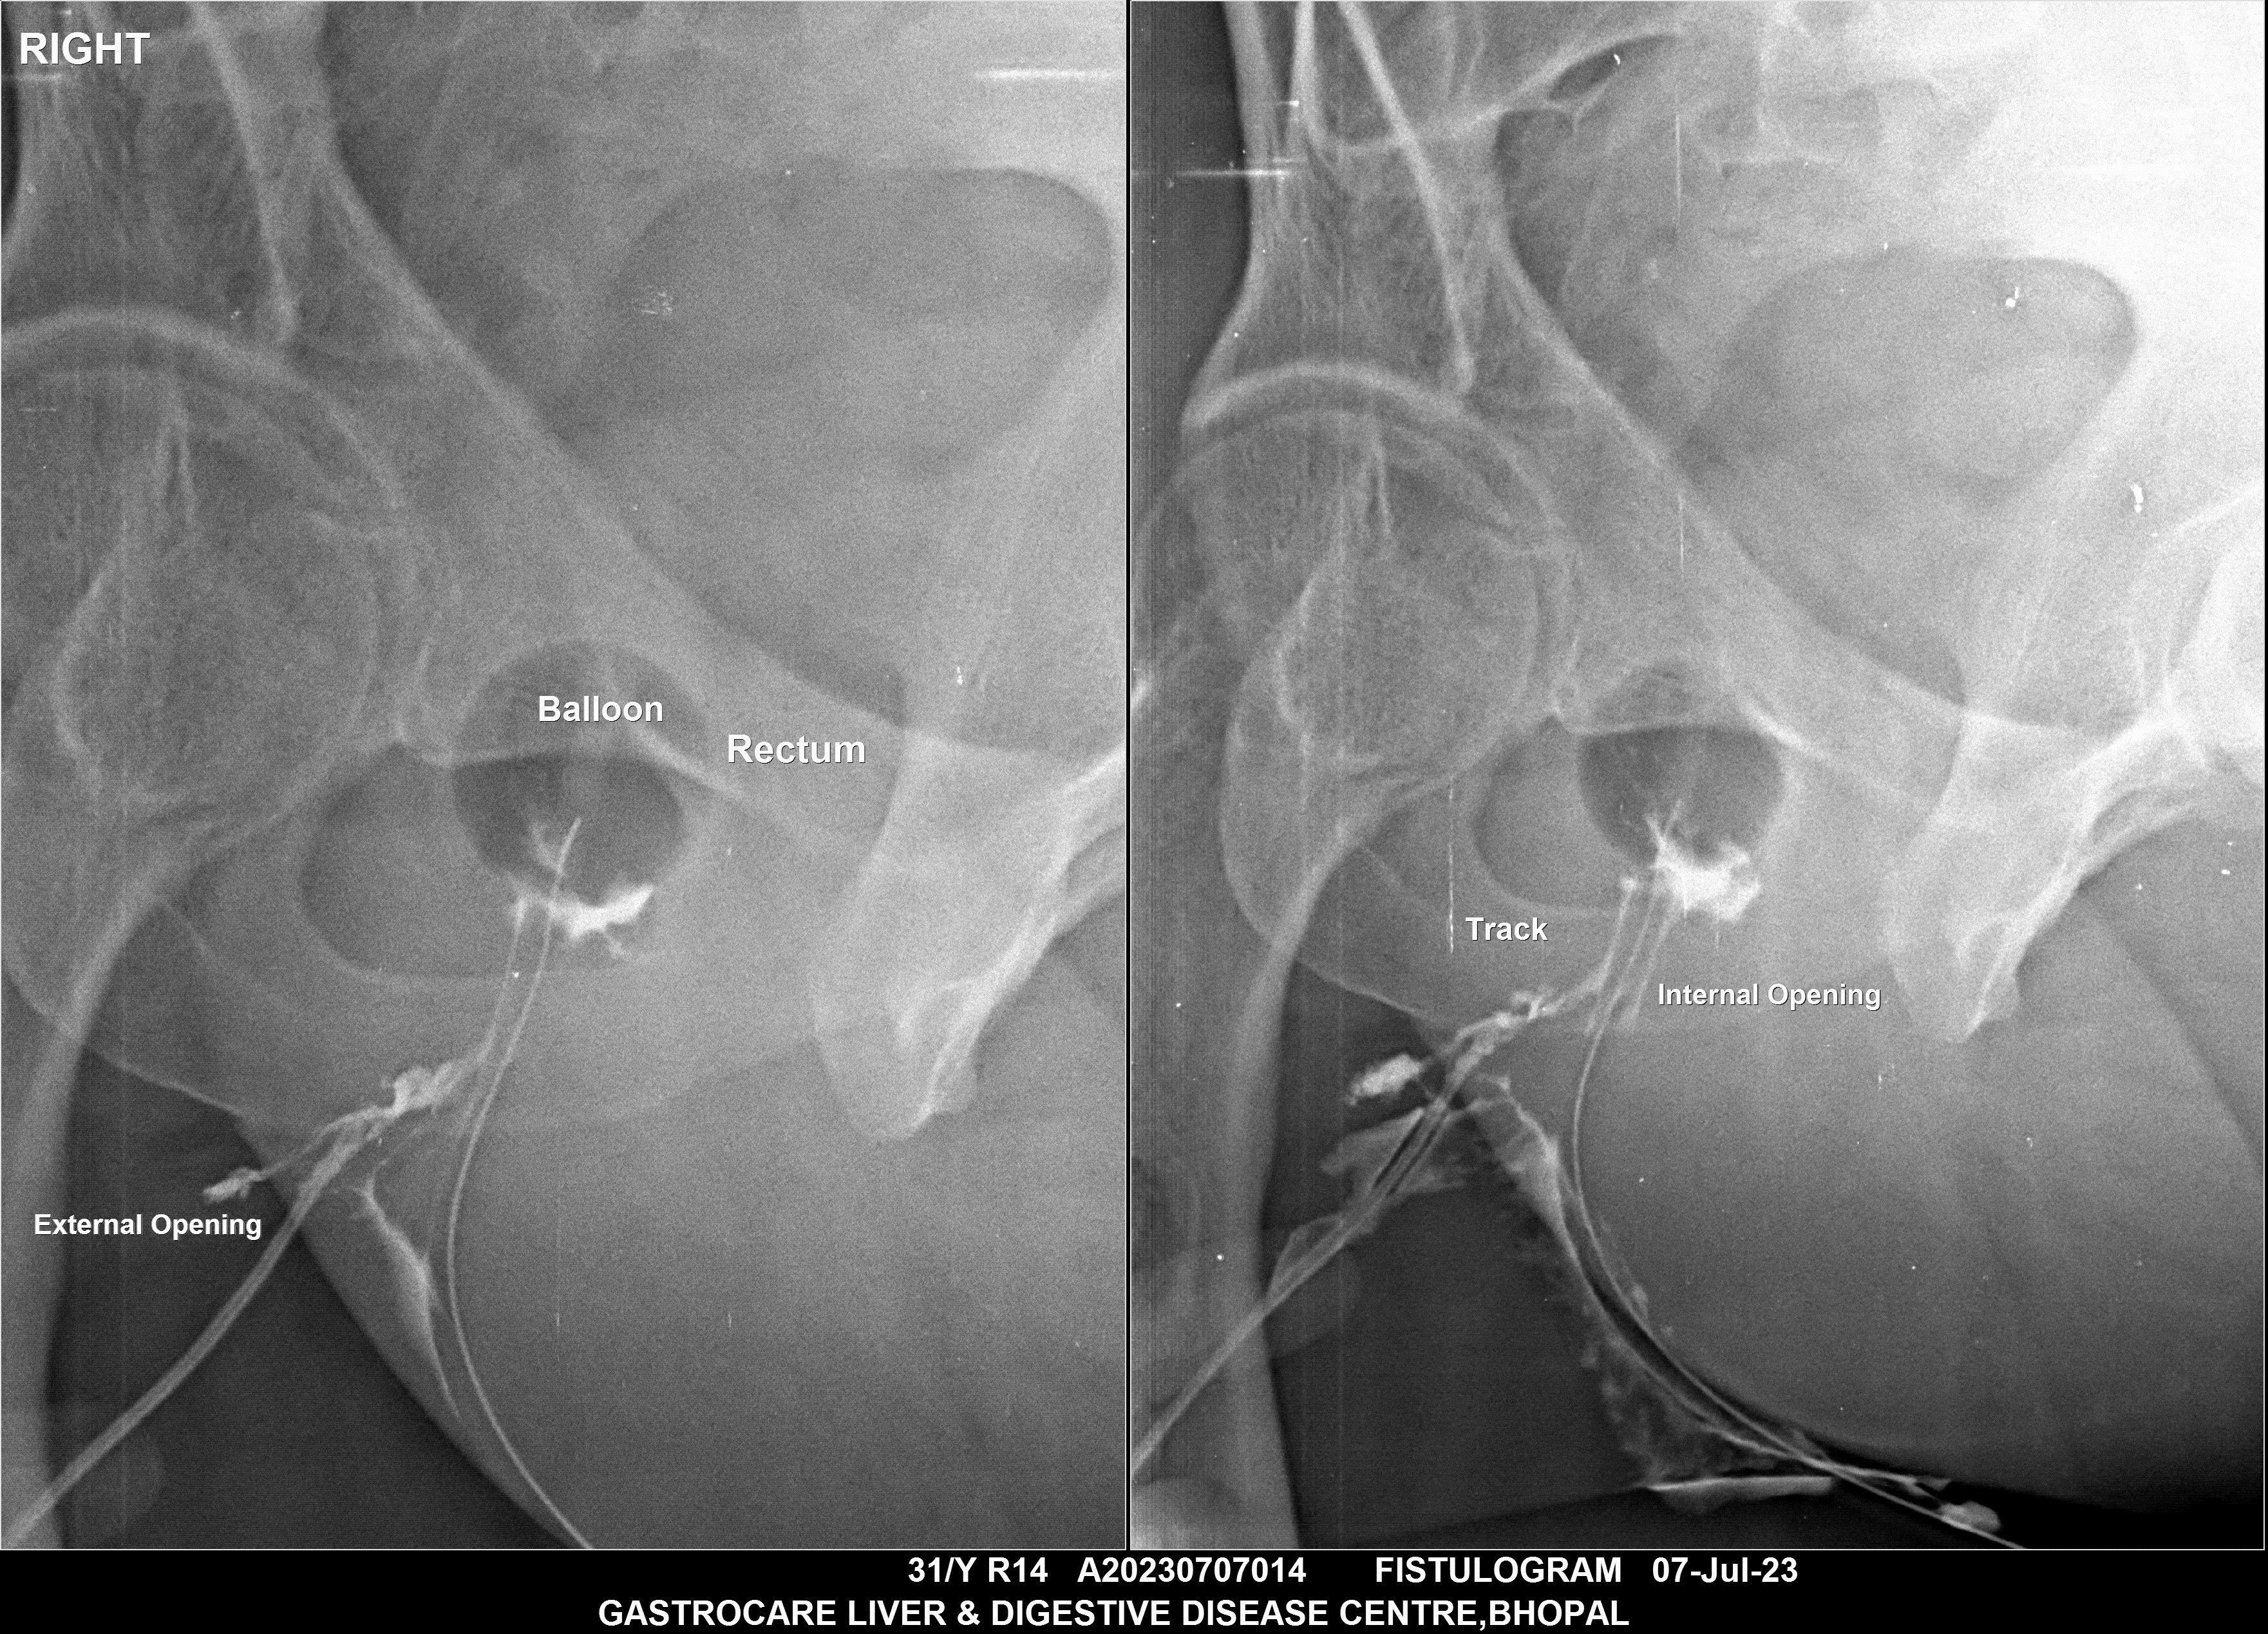

Section: FISTULOGRAM Total: 8 images

BaM Enteroclysis Loopogram BaE Fistulogram Urethrogram HSG